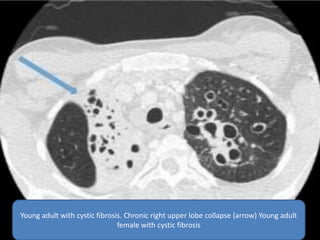

 The most common cause of congenital upper-

lung-predominant bronchiectasis is cystic

fibrosis, commonly associated with enlarged

lung volumes and interstitial alterations. An

autosomal recessive genetic disorder causing

ineffective clearance of secretions, cystic

fibrosis presents with recurrent pneumonias,

sinusitis, pancreatic insufficiency, and

infertility. Milder forms of cystic fibrosis,

however, can remain unrecognized until

adulthood.

Young adult with cystic fibrosis. Chronic right upper lobe collapse (arrow) Young adult

female with cystic fibrosis